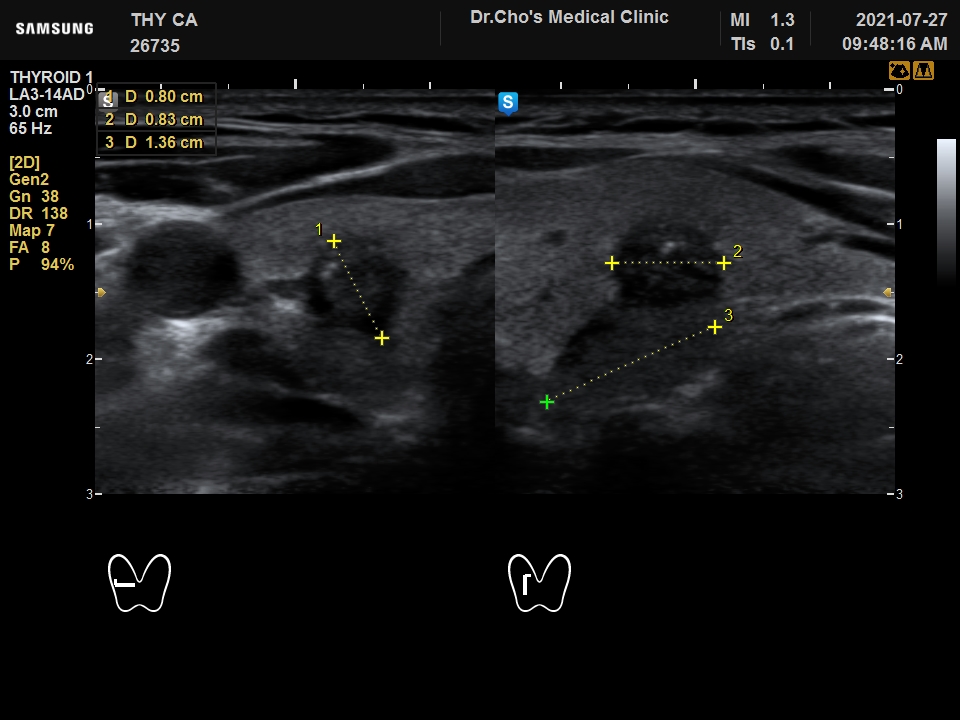

ÃÊÀ½ÆÄ°¶·¯¸®

°©»ó¼± À¯...